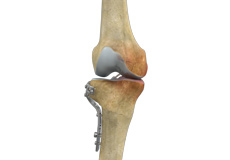

High Tibial Osteotomy

Knee osteotomy is a surgical procedure in which the upper shinbone (tibia) or lower thighbone (femur) is cut and realigned. It is usually performed in arthritic conditions affecting only one side of your knee and the aim is to take pressure off the damaged area and shift it to the other side of your knee with healthy cartilage.